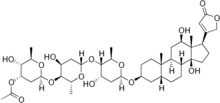

| Formula | C43H66O15 |

| Molar mass | 822.986 g·mol−1 |

α-Acetyldigoxin is a cardiac glycoside. It is an acetyl derivative of digoxin and an isomer of β-acetyldigoxin. It increases the contractility of the heart by its positive inotropic effect on cardiac muscle. The effects of α-acetyldigoxin begin 3–4 hours after administration, and maximize after 6–8 hours. It is prescribed for congestive chronic cardiac failure class II, III and IV.